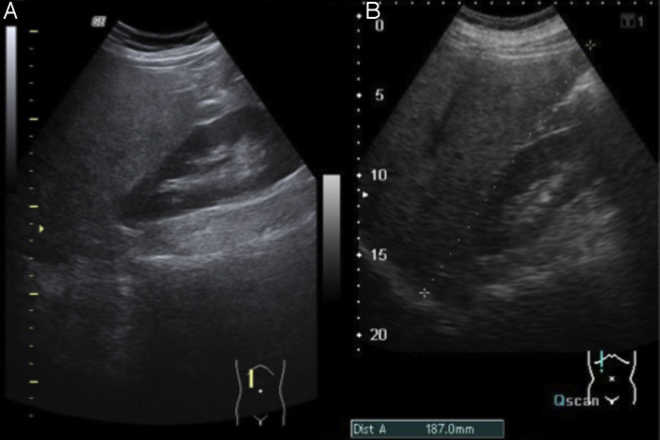

El hígado graso no alcohólico (HGNA) es la principal causa de enfermedad hepática crónica y el síndrome metabólico (SM) es un predictor importante del HGNA. Ante el incremento en la incidencia de SM en México se realizó un estudio transversal los pacientes se les realizó ultrasonido abdominal y se observaron los  lóbulos  hepáticos  evaluando  su  tamaño,  ecogenicidad  y  bordes.  Los  HGNA  encontrados  se  clasificaron  como:  leves,  moderados   o   severos   según   su   grado   de   ecogenicidad   y   la  visualización  de  los  vasos  hepáticos  y  del  diafragma.  La  prevalencia del HGNA se estimó con intervalos de confianza de 95% .Se incluyeron 122 hombres la prevalencia fue màs en hombres que en mujeres sin diferencias de edad.siendo proporcional el porcentaje leve en mayor numero moderado y escasos casos de severo.La prevalencia obtenida es alarmante pues ocho de  cada  diez  individuos  con  SM  tienen  hígado  graso.

Para  detectar  hígado  graso  se  realizó  un  ultrasonido abdominal.Un solo operador certificado realizó todos los ultrasonidos. Los estudios se realizaron con un ultrasonido  marca  Siemens  modelo  Sono  line  versa  plus CC13E71CP700-UM  con  transductor  sectorial,  electrónico, multifrecuencia de 3 a 5MHz.tiempo real en escala de grises. Con el paciente en posición de decúbito dorsal se aplicó gel para mejorar la transmisión del sonido, se observaron el lóbulo hepático derecho,el izquierdo y el caudado evaluando tamaño, ecogenicidad y bordes de hígado. El grado de severidad del hígado graso se clasificó de acuerdo con los siguientes criterios:

Leve.

Mínimo aumento difuso de la ecogenicidad hepática, visualización normal del diafragma y de los bordes de los vasos intrahepáticos.

Moderada. Moderado aumento difuso de la ecogenici

dad hepática, ligera disminución de la visualización de los vasos intrahepáticos y del diafragma.

Severa.Marcado  aumento  de  la  ecogenicidad,  pobre

penetración del segmento posterior del lóbulo hepático

derecho y pobre o nula visualización de los vasos hepáticos y del diafragma